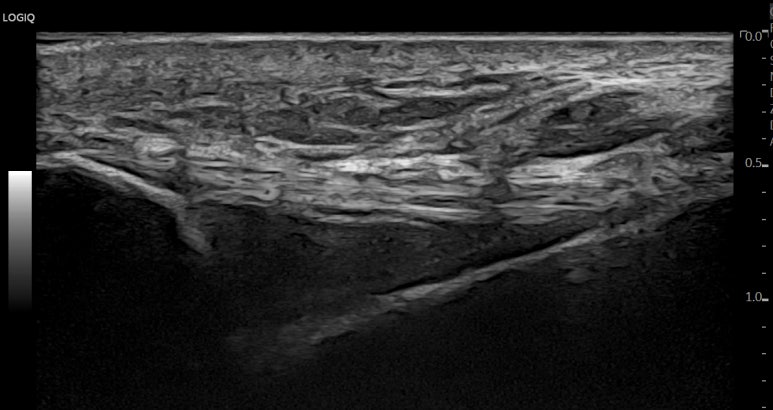

표준 경혈 초음파상

*1) 비슷한 두께로

*2) 직선으로 주행하면서

3) 인대 내부 섬유 패턴이

보여야 하죠.